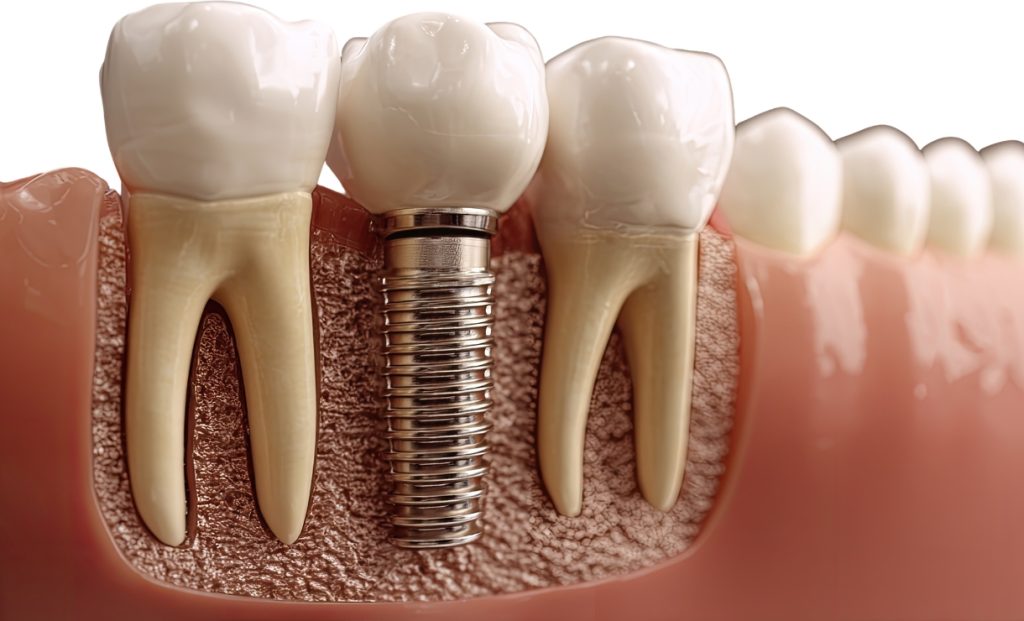

Perder um dente pode ser uma experiência frustrante e impactante na vida de qualquer pessoa. A busca por uma “protese dentaria” muitas vezes começa quando nos damos conta do impacto que a falta de um ou mais dentes pode ter, não apenas na estética do sorriso, mas também na mastigação e na autoestima. Felizmente, a […]